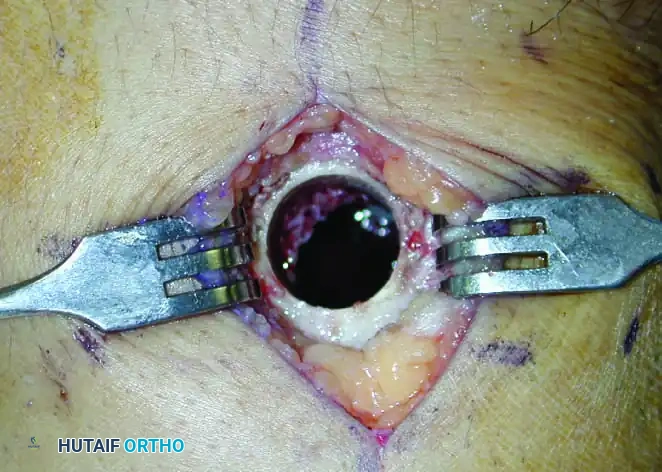

- Cortical Window Creation: A high-speed burr or osteotome is used to create a cortical window large enough to visualize the entire cavity.

Figure 2: Intraoperative photograph demonstrating a meticulously prepared circular cortical window. Note the smooth edges designed to minimize stress risers and prevent iatrogenic fracture.

- Intralesional Excision: Using a series of progressively sized curettes, the tumor is systematically evacuated. The surgeon must meticulously scrape the walls of the cavity until normal, healthy cancellous bone is encountered.